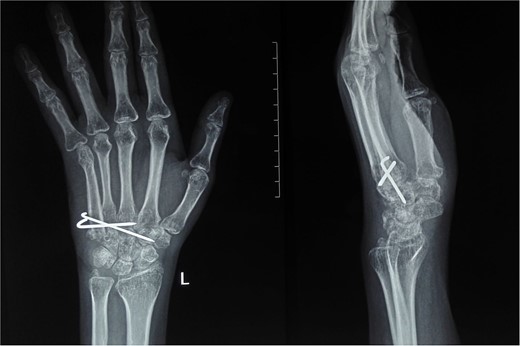

On physical examination, there was a firm, fusiform swelling over the fifth metacarpal without skin changes or tenderness. The range of motion in adjacent joints was preserved. Radiographs revealed a large, expansile lytic lesion in the diaphysis of the fifth metacarpal, with cortical thinning-indicative of recurrent GCT (Fig. 1). A biopsy confirmed the diagnosis.

X-ray of the right hand shows an expansile, lytic lesion in the diaphysis of the fifth metacarpal with a “paper-thin” cortex extending to the subchondral bone.